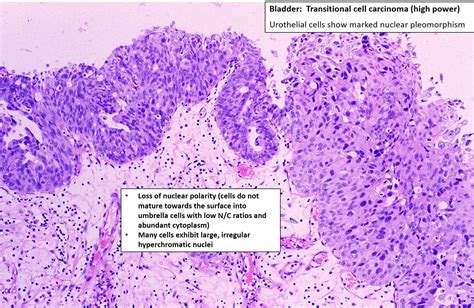

Transitional Cell Carcinoma

Bladder Transitional Cell Carcinoma, Light Micrograph Stock Image Image of neoplas, morphology